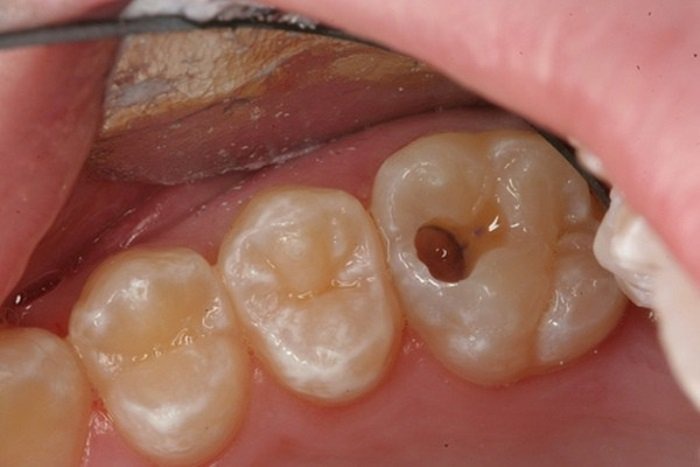

Viêm quanh chóp răng mạn tính là tình trạng nhiễm trùng kéo dài ở vùng mô quanh chóp răng, thường do tủy răng hoại tử không được điều trị đúng cách. Đây chính là “tiền thân” của nhiều trường hợp nang chân răng, và nếu ổ viêm này không được giải quyết triệt để, nang hoàn toàn có thể hình thành trở lại sau phẫu thuật.

- Nạo nang không triệt để, còn sót mô biểu mô bệnh lý

- Không điều trị tủy răng hoặc điều trị tủy thất bại